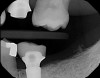

Integrative digital planning can also lead to quicker and more efficient treatment times for dental implant therapy. Another patient presented for a dental implant to replace tooth No. 19 at the end of orthodontic treatment. By leveraging 3D planning (Figure 13) and the printing of a surgical guide, the patient's implant was placed using a flapless approach. At the time of placement, an intraoral scan body was placed on the implant and digital impressions were made for her final restoration (Figure 14). At 10 weeks, the final custom abutment and CAD/CAM crown were delivered, all digitally fabricated without the use of physical models (Figure 15 through Figure 17). For implant placement and restoration, the patient had two visits, with a total chair time of 65 minutes, and no need for anesthetic at the second visit.

Fig 13. Prosthetically driven planning of implant placement No. 19.

Figure 13

Fig 14. Scan body after No. 19 implant placement.

Figure 14

Fig 15. Custom titanium abutment No. 19 at delivery.

Figure 15

Fig 16. Final crown No. 19 delivered.

Figure 16

Fig 17. Radiograph showing final restoration for implant No. 19.

Figure 17